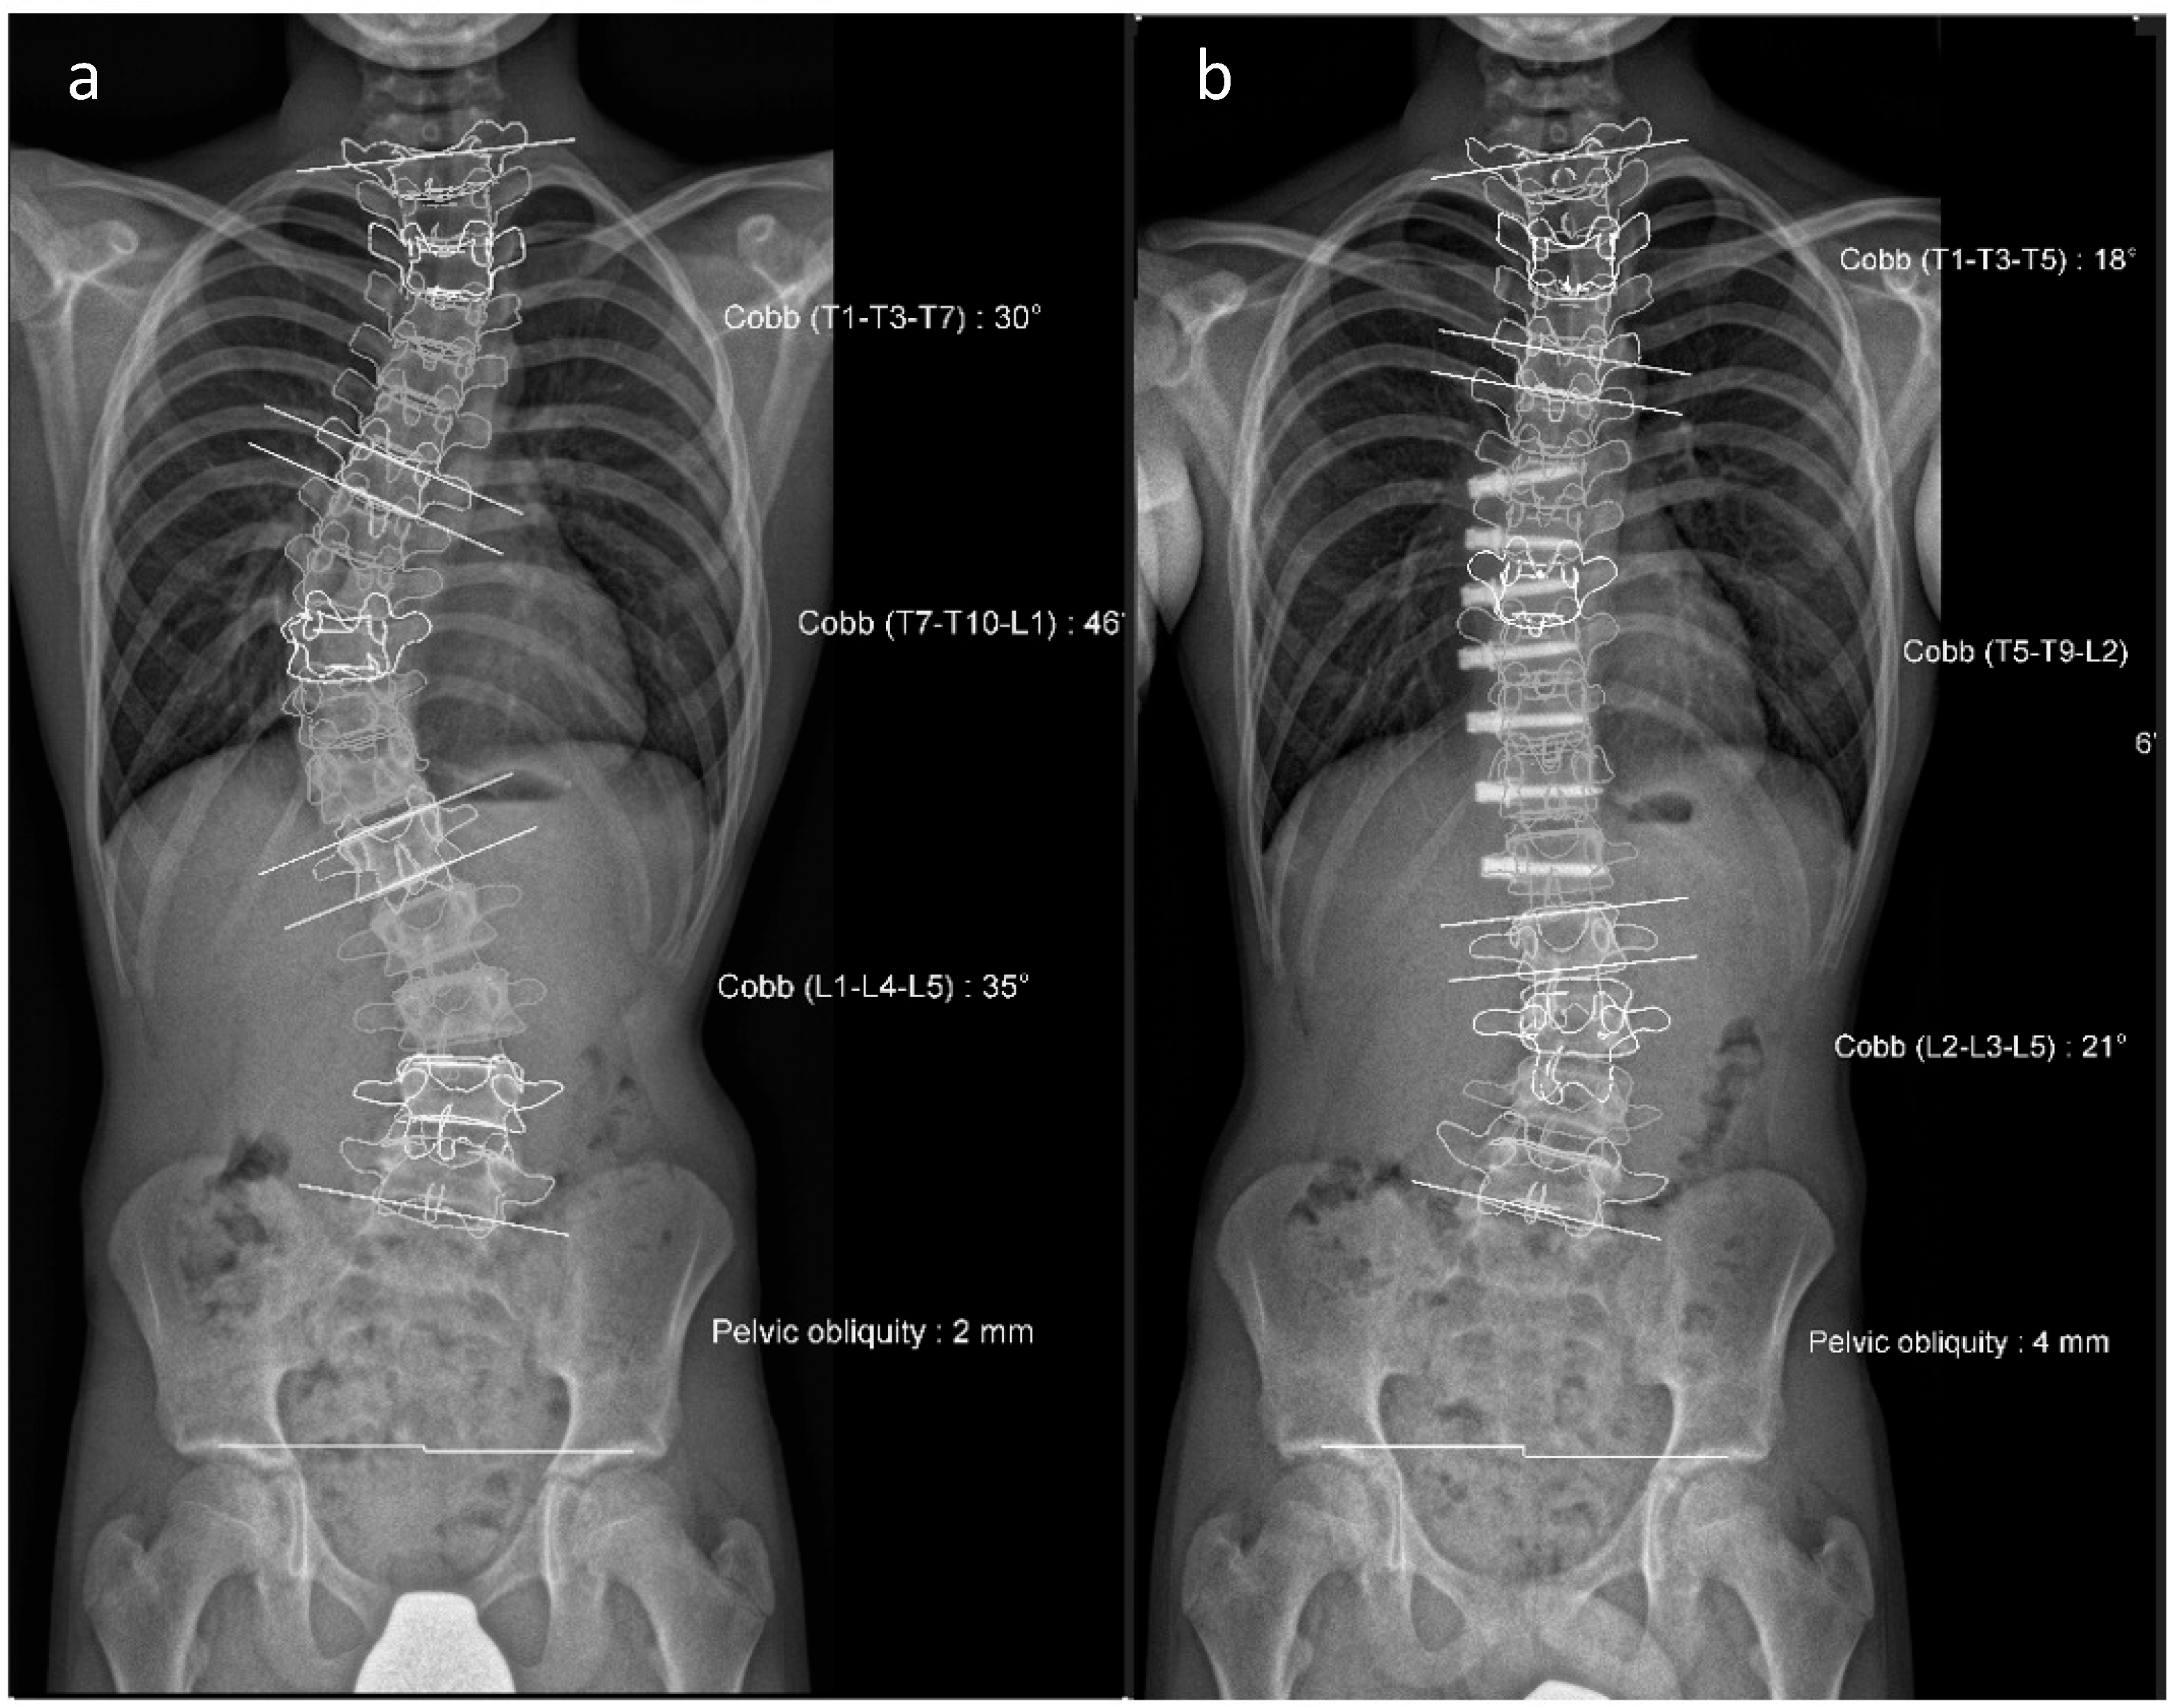

Figure 5. (a,b). Initial radiographs of a patient with adolescent idiopathic scoliosis. (c,d). Bending radiographs. (e,f). Postoperative image displaying implanted magnetically controlled growing rods as a dual rod system. (g,h). The patient was treated with a spondylodesis upon the completion of growth to maintain correction success (Reprinted with permission [10]).

To avoid the regular surgical lengthening procedure, MCGRs were developed and approved for the treatment of EOS in Europe in 2009. MCGRs are telescopically extendable distraction rods. They can be distracted non-invasively, on an outpatient basis, by externally magnetically controlled lengthening using electromagnets. Figure 5 illustrates the progression of treatment for a patient with AIS, starting from initial diagnosis, through the bending radiographs, to the postoperative phase with implanted MCGR, and finally, the maintenance phase involving spondylodesis.